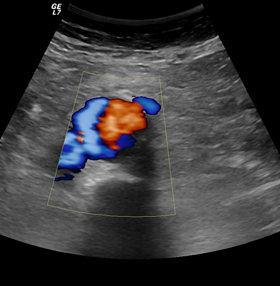

Triplex αγγείων

Για τα Triplex

• Καρωτίδων και σπονδυλικών αρτηριών

• Αρτηριών άνω και κάτω άκρων

• Φλεβών άνω και κάτω άκρων

• Οσχέου

Δεν απαιτείται προετοιμασία.

Ενώ για τα Triplex

• Νεφρικών αρτηριών

• Πυλαίας φλέβας (σπληνοπυλαίου άξονα)

• Κοιλιακής αορτής

• Λαγονίων αρτηριών

• Έλεγχος και παρακολούθηση θεραπευτικών επεμβάσεων (παρακαμπτήρια μοσχεύματα, stent) διαφόρων αγγείων στην κοιλιά